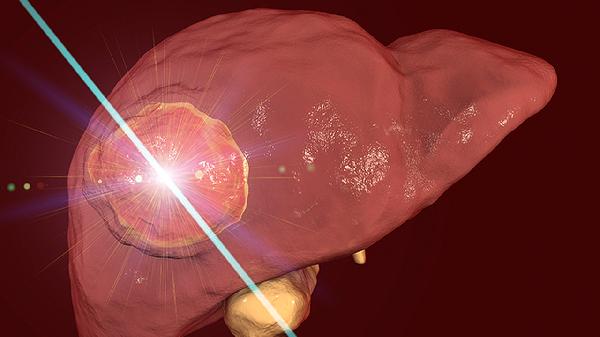

2、手术切除适用于恶性或无法确定性质的结节。胸腔镜手术创伤小,恢复快;开胸手术适合较大或位置复杂的结节;射频消融术可用于小范围结节。手术方式需根据结节大小、位置及患者身体状况选择。